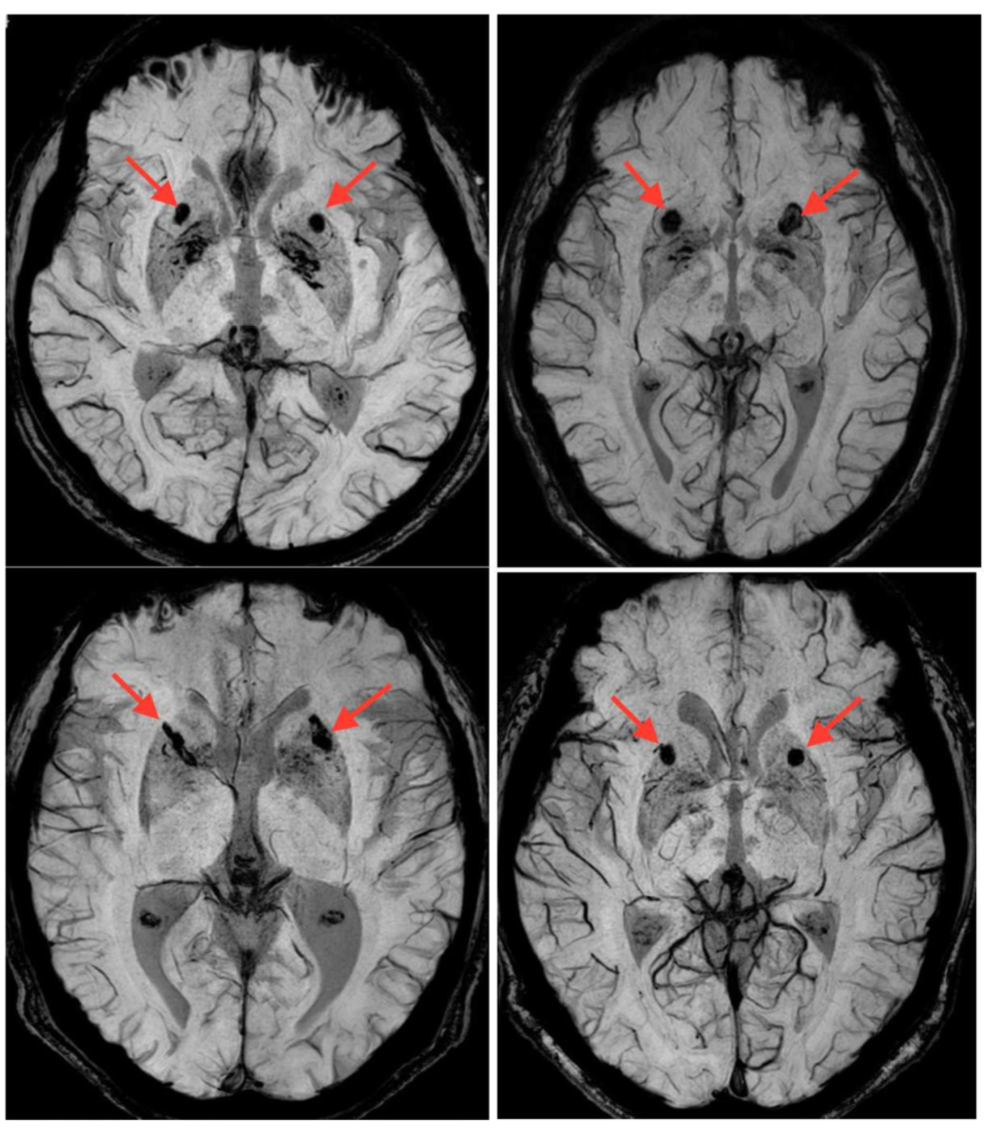

2017年,科學家用同樣的方式將120個帶有豬腦細胞的膠囊植入了病人腦部。一共有18個病程至少5年的老年人蔘與了實驗。

CT下移植入人腦的膠囊位置

植入手術18個月後,根據受試者的主觀感受,帕金森的各項症狀得到改善。最重要的是,沒有發現患者變蠢。這估計是大家最關心的問題吧